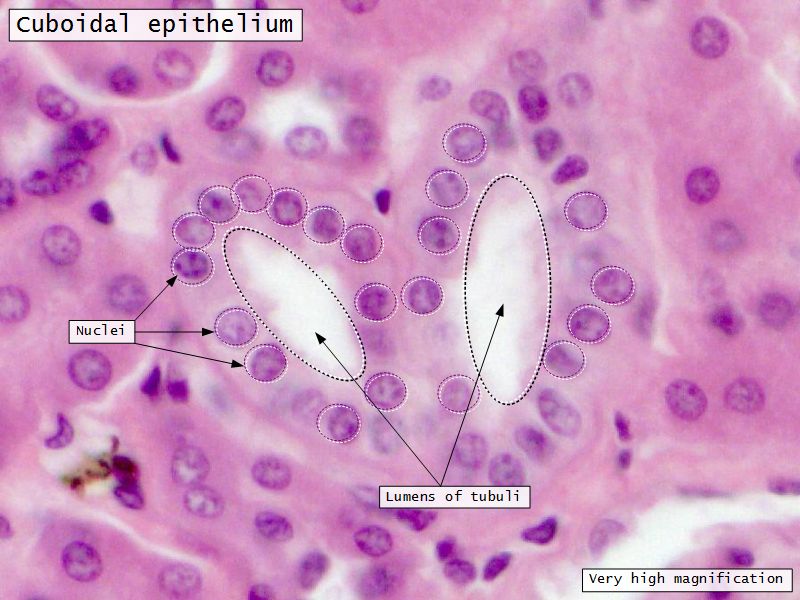

Loop of Henle - thin

- Narrow lumen

- Thin wall

- Squamous epithelium

- Looks like capillaries

Loop of Henle - thick

Continuation of descending and ascending tubuliDistal convoluted tubuli

- Joins collecting tubule

- Cuboidal epithelium

- Light stained

- Wide looking lumen

- Indistinct borders